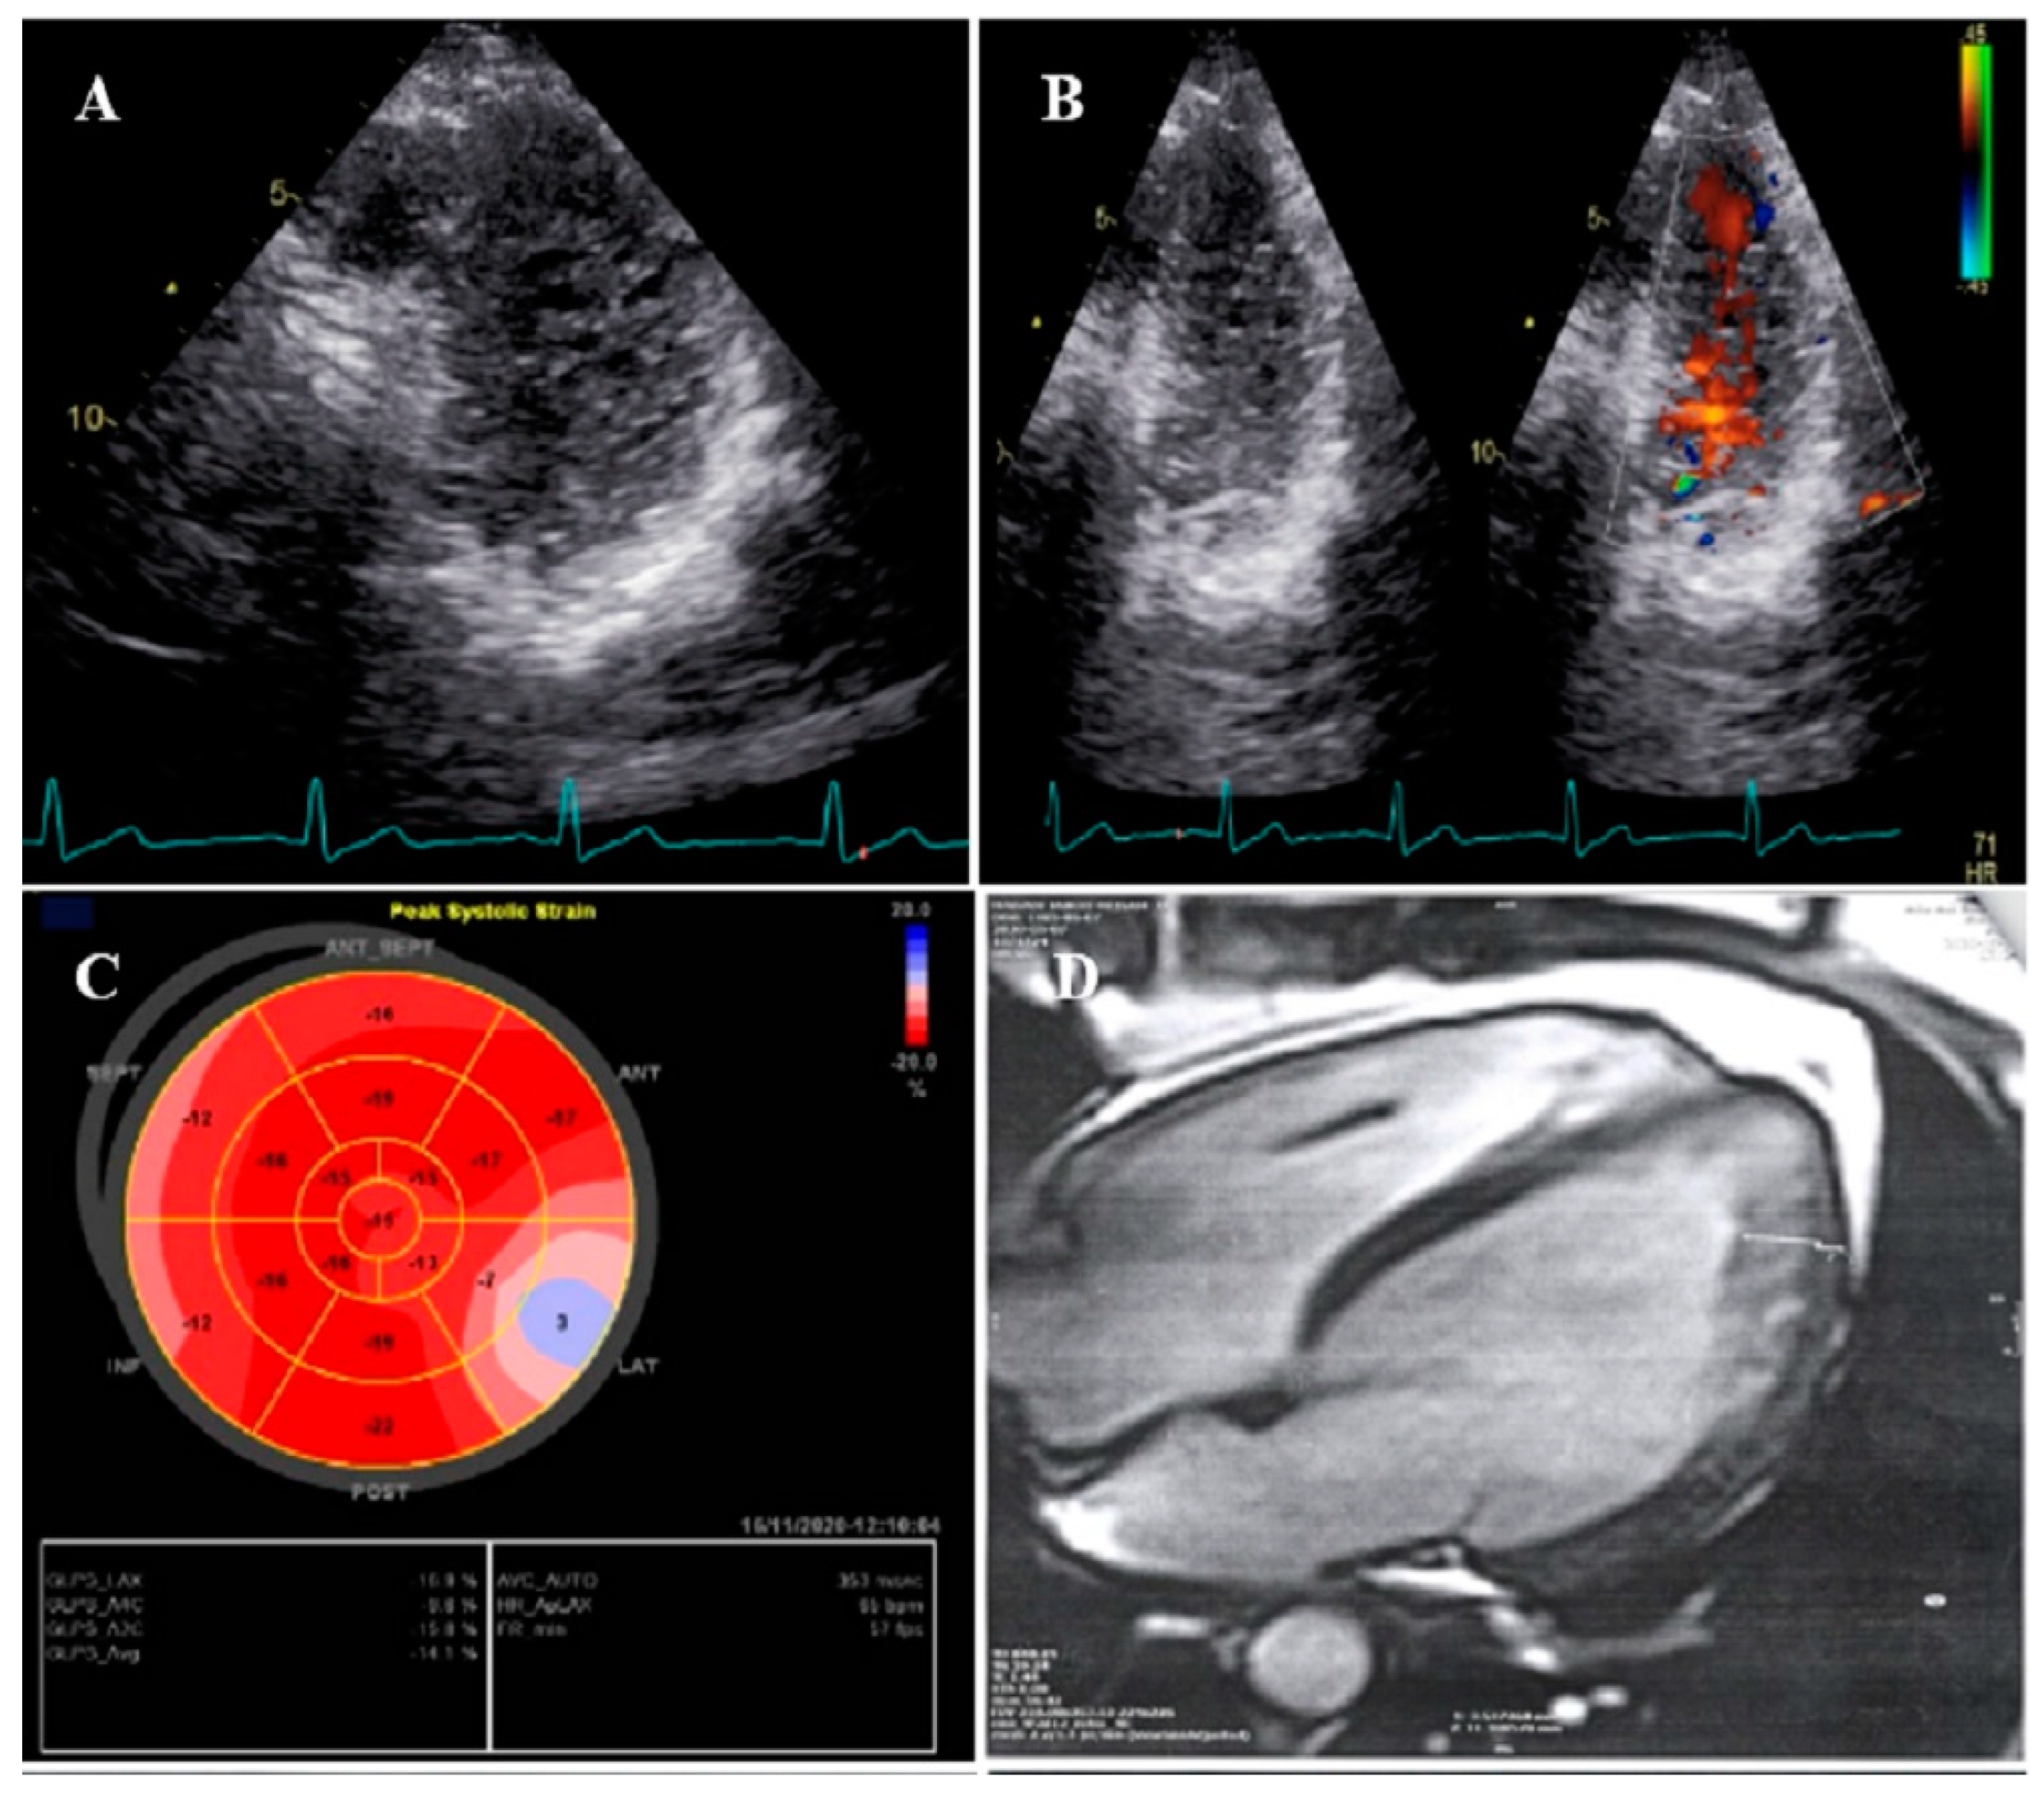

2.6. Case #6. BVNC, Bicuspid Aortic Valve (BAV), and Proximal Muscle Weakness in Lower Extremities

A 43-year-old gentleman with a complaint of dyspnea on exertion and recently at rest was referred to our hospital. He was labeled as a case of biventricular failure for months by another colleague, who prescribed anti-heart failure medications for him (daily furosemide 40 mg, spironolactone 25 mg, losartan 25 mg, and carvedilol 12.5 mg), medications which have resulted in no marked improvements in his symptoms. He reported generalized weakness and a physical examination revealed proximal muscle weakness in both lower extremities without atrophy. TTE findings were compatible with non-compaction of the left and right ventricles with severe biventricular systolic dysfunction (LVEF = 24% and functional area change = 16%) and BAV (Figure 6). STE showed severe mechanical impairment of myocardial performance in all segments (GLS = −3.3%). He left the hospital because of the lack of insurance coverage and financial problems; therefore, we were unable to evaluate whether his muscle weakness was related to NCLV or not.

Figure 6.

Two-dimensional transthoracic echocardiographic views of case #6. (A,B); Biventricular non-compaction in apical four-chamber and SAX views. (C,D); Thick, bicuspid aortic valve with diastolic closure doming; PLAX zoomed-out and zoomed-in views. (E); Diastolic closure and systolic opening in SAX view. (F,G); Speckle tracking echocardiography, illustrating severe myocardial performance impairment in all segments with GLS of −3.3%. (H,I); Patient’s difficulty in going up and down the stairs because of weakness in the proximal muscles, when he was asked not to use the stair railing.